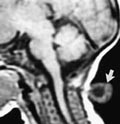

Tumorer med innvekst til sentralnervesystemet, for eksempel fra øre-nese-hals-området, kan nøyaktig kartlegges med MR, og operabilitet kan vurderes enklere og sikrere enn ved CT med aksiale snitt (fig 3). Ved å kombinere MR med ultralydveiledet biopsi og beinmargsprøver, samt ev. CT i samme seanse, spares barnet for flere narkoser. En slik integrering av MR-undersøkelse i utredningsrekken blir stadig oftere etterspurt hos barn.